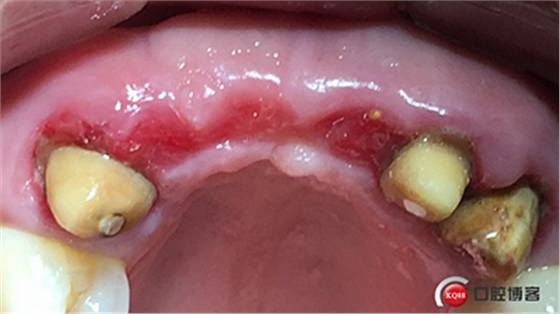

水平切口,鄰牙冠延長(zhǎng)。

大家注意這個(gè)動(dòng)作,雖然不翻瓣,但要將唇側(cè)倒凹處骨膜剝離。

將骨粉塞入剝離的骨膜下間隙里既唇側(cè)倒凹處,盡量塞滿。